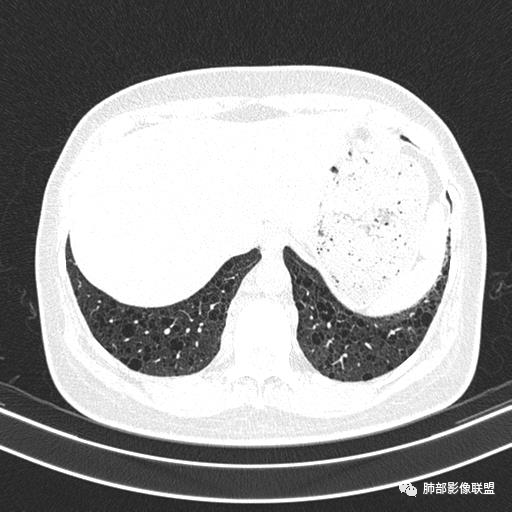

中年女性,不吸烟

双肺弥漫囊腔,累及肋膈角,囊腔形态相对规则单一。

符合LAM

CT平扫示双肺弥漫分布大小不等囊状薄壁透光区,无内、中、外带分布差异,间质稍示增厚。拟LAM

我也支持刘老师。中年女性,咳嗽气喘,有苯吸入史,双肺野多发囊腔,囊腔形态相对规则,大小不一,壁薄,有的似无壁,双肺弥漫磨玻璃影,有间质性改变,育龄期女性,首选考虑lam,但是患者有吸入苯病史半年,囊腔形态不是很规则,大小不一,分布不均匀,有的无壁似小叶中央肺气肿,有弥漫性磨玻璃及间质性改变,不排除吸入引起的间质性肺炎?

中年女性,双肺弥漫性磨玻璃密度影,并见弥漫性分布大小不一囊腔,壁薄,形态规则,考虑lam,鉴别苯中毒肺损伤致间质改变

中年女性育龄期妇女,咳嗽气喘,无吸烟史,有苯吸入史。影像:双肺弥漫均匀小囊腔,无明显分布优势,囊腔形态欠规则,壁薄,部分囊腔边缘血管征,伴双肺弥漫磨玻璃影,无结节,考虑lam,鉴别苯中毒肺损伤,囊腔多有分布优势,小叶中心分布为主,形态规整等

中年女性,两肺弥漫分布囊性低密度影,壁薄,相对规则,境界尚清晰,考虑LAM

中年育龄期女性,双肺多发含气囊腔弥漫性分布,囊间肺组织结构正常,常规考虑Lam

女,46,活动性气喘1年。苯吸入史半年。胸部CT:两肺弥漫囊腔,上至肺尖,下至肋膈角,形态类似小囊腔。考虑:LAM,鉴别LIP,BHD,PLCH等。

双肺弥漫大小不一薄壁含气囊腔,囊间肺组织正常,正常肺背景,肺尖肺底受累;青年女性,气喘,支持LAM

双肺多发大小相近的囊状影,分布趋势趋于一致,中年女性,考虑LAM。部分囊内见血管及分隔影,小叶中心性肺气肿代排

CT表现:双肺弥漫大小不等的薄壁囊腔,囊壁<2mm,外形规则,血管影多位于囊腔周围,囊腔之间肺组织正常,随着疾病进展到晚期,囊腔变大、增多,不可胜数,囊腔可融合成较大的囊,与肺气肿相似,形成间质性肺纤维化。部分病例可出现结节影。